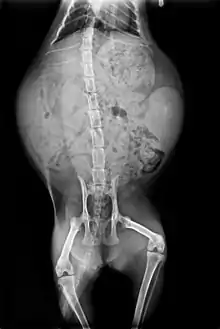

يوجد لدى القطط 7 فقرات عنقية (مثل معظم الثدييات)، و13 فقرة صدرية (لدى البشر 12)، و7 فقرات قطنية (لدى البشر 5) و3 فقرات عجزية (مثل معظم الثدييات، ولكن لدى البشر 5)، وعدد متغير من الفقرات في الذيل (لدى البشر فقط فقرات ذيلية أثرية لا وظيفية، مدمجة في العصعص الداخلي).[57] تفسر الفقرات القطنية والصدرية الزائدة حركية القطط ومرونتها. يتصل بالعمود الفقري 13 ضلعا مع الكتف والحوض.[57] على عكس الأذرع البشرية فإن الأطراف الأمامية للقطط متصلة بالكتف عن طريق عظام الترقوة التي تتحرك بحرية مما يسمح لها بتمرير أجسامها عبر أي مساحة يمكن أن تناسب رؤوسها.[58]

الهيكل العظمي